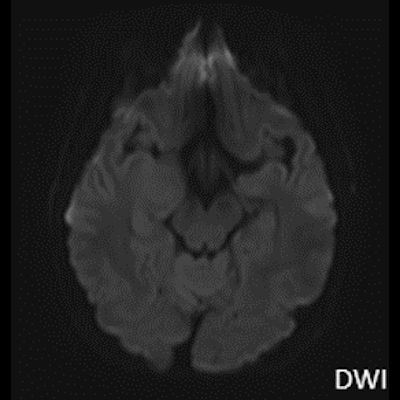

- A) Sağ temporal lob anteromedialinde silik sınırlı BT’de hipodens (ok), MRG’de T2AG ve FLAIR hiperintens (oklar), T1AG izo-hipointens (ok) sinyal özelliğinde ekspansil kitlesel lezyon izlenmektedir.

- B) Lezyon difüzyon görüntüde izo-hiperintens, ADC haritalamada hafif hiperintens izlenmiş olup (oklar) diffüzyon kısıtlılığı göstermemektedir. Lezyonun anterior kesiminde kontrastlı serilerde yamalı kontrast tutulumları (oklar) mevcuttur. MR spektroskopide lezyon düzeyinden elde olunan multivoksel görüntülerde kolin pikinde artış ve NAA da azalma (oklar) dikkati çekmektedir. Kolin/kreatinin oranı 1.76 olarak ölçülmüştür.